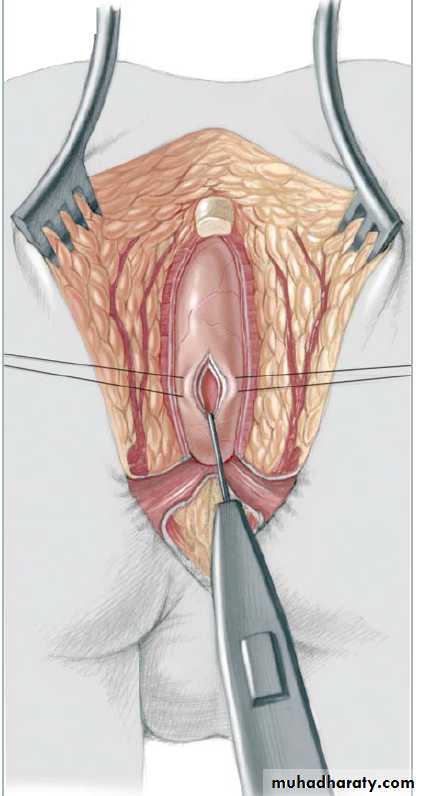

3-4 month later definitive surgery using posterior sagital anorectoplasty(P.S.A.R.P. pullthrogh) Or penna technique.

- Recently laparoscopic pull through using nerve stimulator to identify anal sphincter ,

-the sphincter is not well developed and nerve supply is deficient= continence not good.- 2 months later colostomy closed.

- Regular anal dilatation.